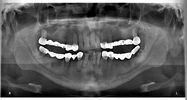

د. فولكان أوزدمير – طبيب أسنان

طبيب أسنان